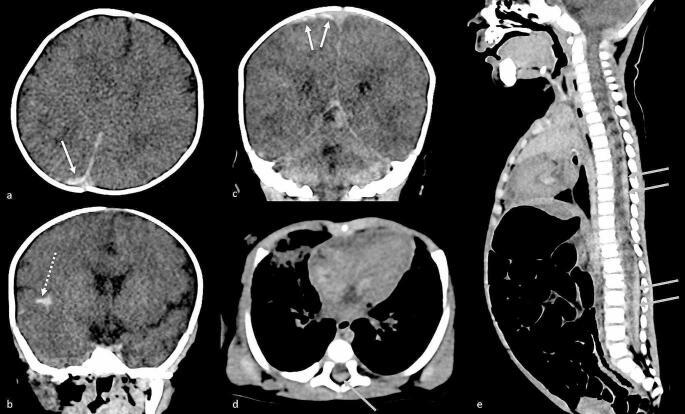

In living children, the use of a wide field fundus camera such as RetCam is the gold standard practice to document retinal haemorrhages in suspected cases of abusive head trauma (AHT). In case of sudden unexpected death in infancy (SUDI), child abuse must be considered as a possible cause of death and an eye examination is required. However, no example of post-mortem fundus photograph (PMFP) of retinal haemorrhages related to AHT is yet available for clinicians.We report a SUDI case, with no external traumatic lesions or limb fractures, for which prompt PMFP showed retinal haemorrhages typical of AHT: child abuse was subsequently confirmed by the forensic investigation. We discuss why PMFP is a relevant screening test to detect retinal haemorrhages in the case of SUDI and why the use of the RetCam should be further investigated.

在存活的儿童中,使用广角眼底相机(如 RetCam)是记录疑似虐待性头部创伤(AHT)的视网膜出血的金标准方法。对于婴儿猝死(SUDI),必须考虑虐待作为可能的死亡原因,并且需要进行眼部检查。然而,目前还没有与 AHT 相关的死后眼底照片(PMFP)的例子可供临床医生使用。我们报告了一个 SUDI 病例,没有外部创伤性病变或肢体骨折,及时的 PMFP 显示出典型的 AHT 视网膜出血:随后法医调查证实了虐待行为。我们讨论了为什么 PMFP 是检测 SUDI 情况下视网膜出血的相关筛查测试,以及为什么应该进一步研究 RetCam 的使用。